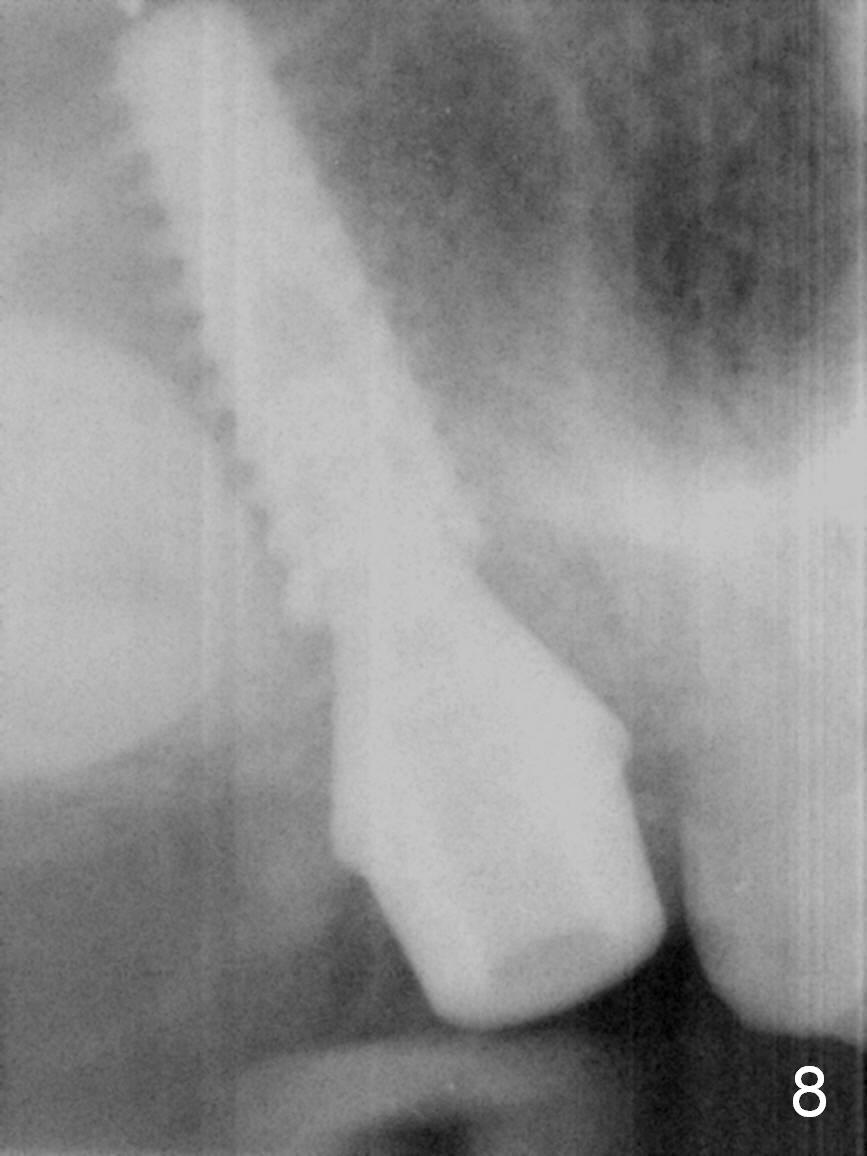

Extraction confirms crack tooth at #2 (Fig.1 (mesial view) <). The buccal (Fig.2 (illustration) B) socket is larger than the palatal (P) one, while the septum (S) is small. Osteotomy is initiated on the buccal slope of the septum (Fig.3 red arrow), followed by Magic osteotomes (Fig.4-7). As the diameter of the osteotomes increases, so does the depth with sinus lift (Fig.5 arrow). The largest osteotome is 4.8 mm. When a 5x13 mm implant is placed, it has low torque (Fig.8,9). The implant resists lateral movement, but keeps turning. When a largest pair abutment with the longest cuff is placed (6.5x4(4) mm to hold an immediate provisional in place), it seems to turn with the underlying implant together for a half turn. Since the provisional is engaged into the distal undercut of the tooth #3 (while the acrylic is setting), it may increase the implant stability. Anyway, overprep in this case leads to low primary stability. For immediate implant, underprep is a must. For this case, the last osteotome should have been 4.3 mm (.7 mm (one or two size(s)) smaller than the implant). When the implant is found to have low torque value, remove it, place bone graft in the osteotomy site and surrounding socket for sinus lift as well and place the implant again. The primary stability should have been increased. Preferably, a larger implant should be used (5.5 mm). Fortunately there is nasal hemorrhage postop. Reexamination of the extracted tooth after being soaked in bleach for 2 days confirms that the mesial (Fig.10 M) and distal (Fig.11 D,12 <) crack lines extend intrapulpally (^).